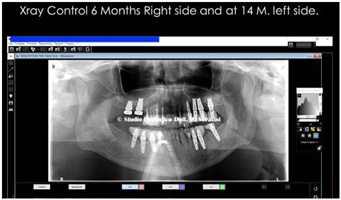

Control at six months on the right side and at 14 months on the left side, after finalization (Figure 27).

Figure 27: Control at six months on the right side and at 14 months on the left side.